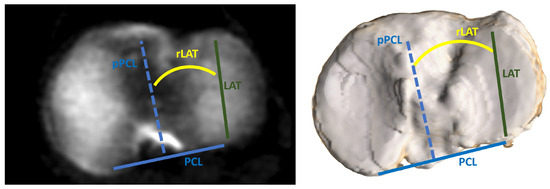

| tF, ° | 12.3 ± 7.7 (−13.2–34.2) |

| tT, ° | −25.9 ± 8.4 (−57.5–-4.4) |

| Medial tibial slope, ° | 82.8 ± 3.8 (70.7–92.7) |

| Lateral tibial slope, ° | 84.1 ± 3.7 (72.3–95.2) |

| rFT, ° | −6.7 ± 4.7 (−19.1–3.7) |

| rLAT, ° | −6.5 ± 3.3 (−13.0–3.8) |